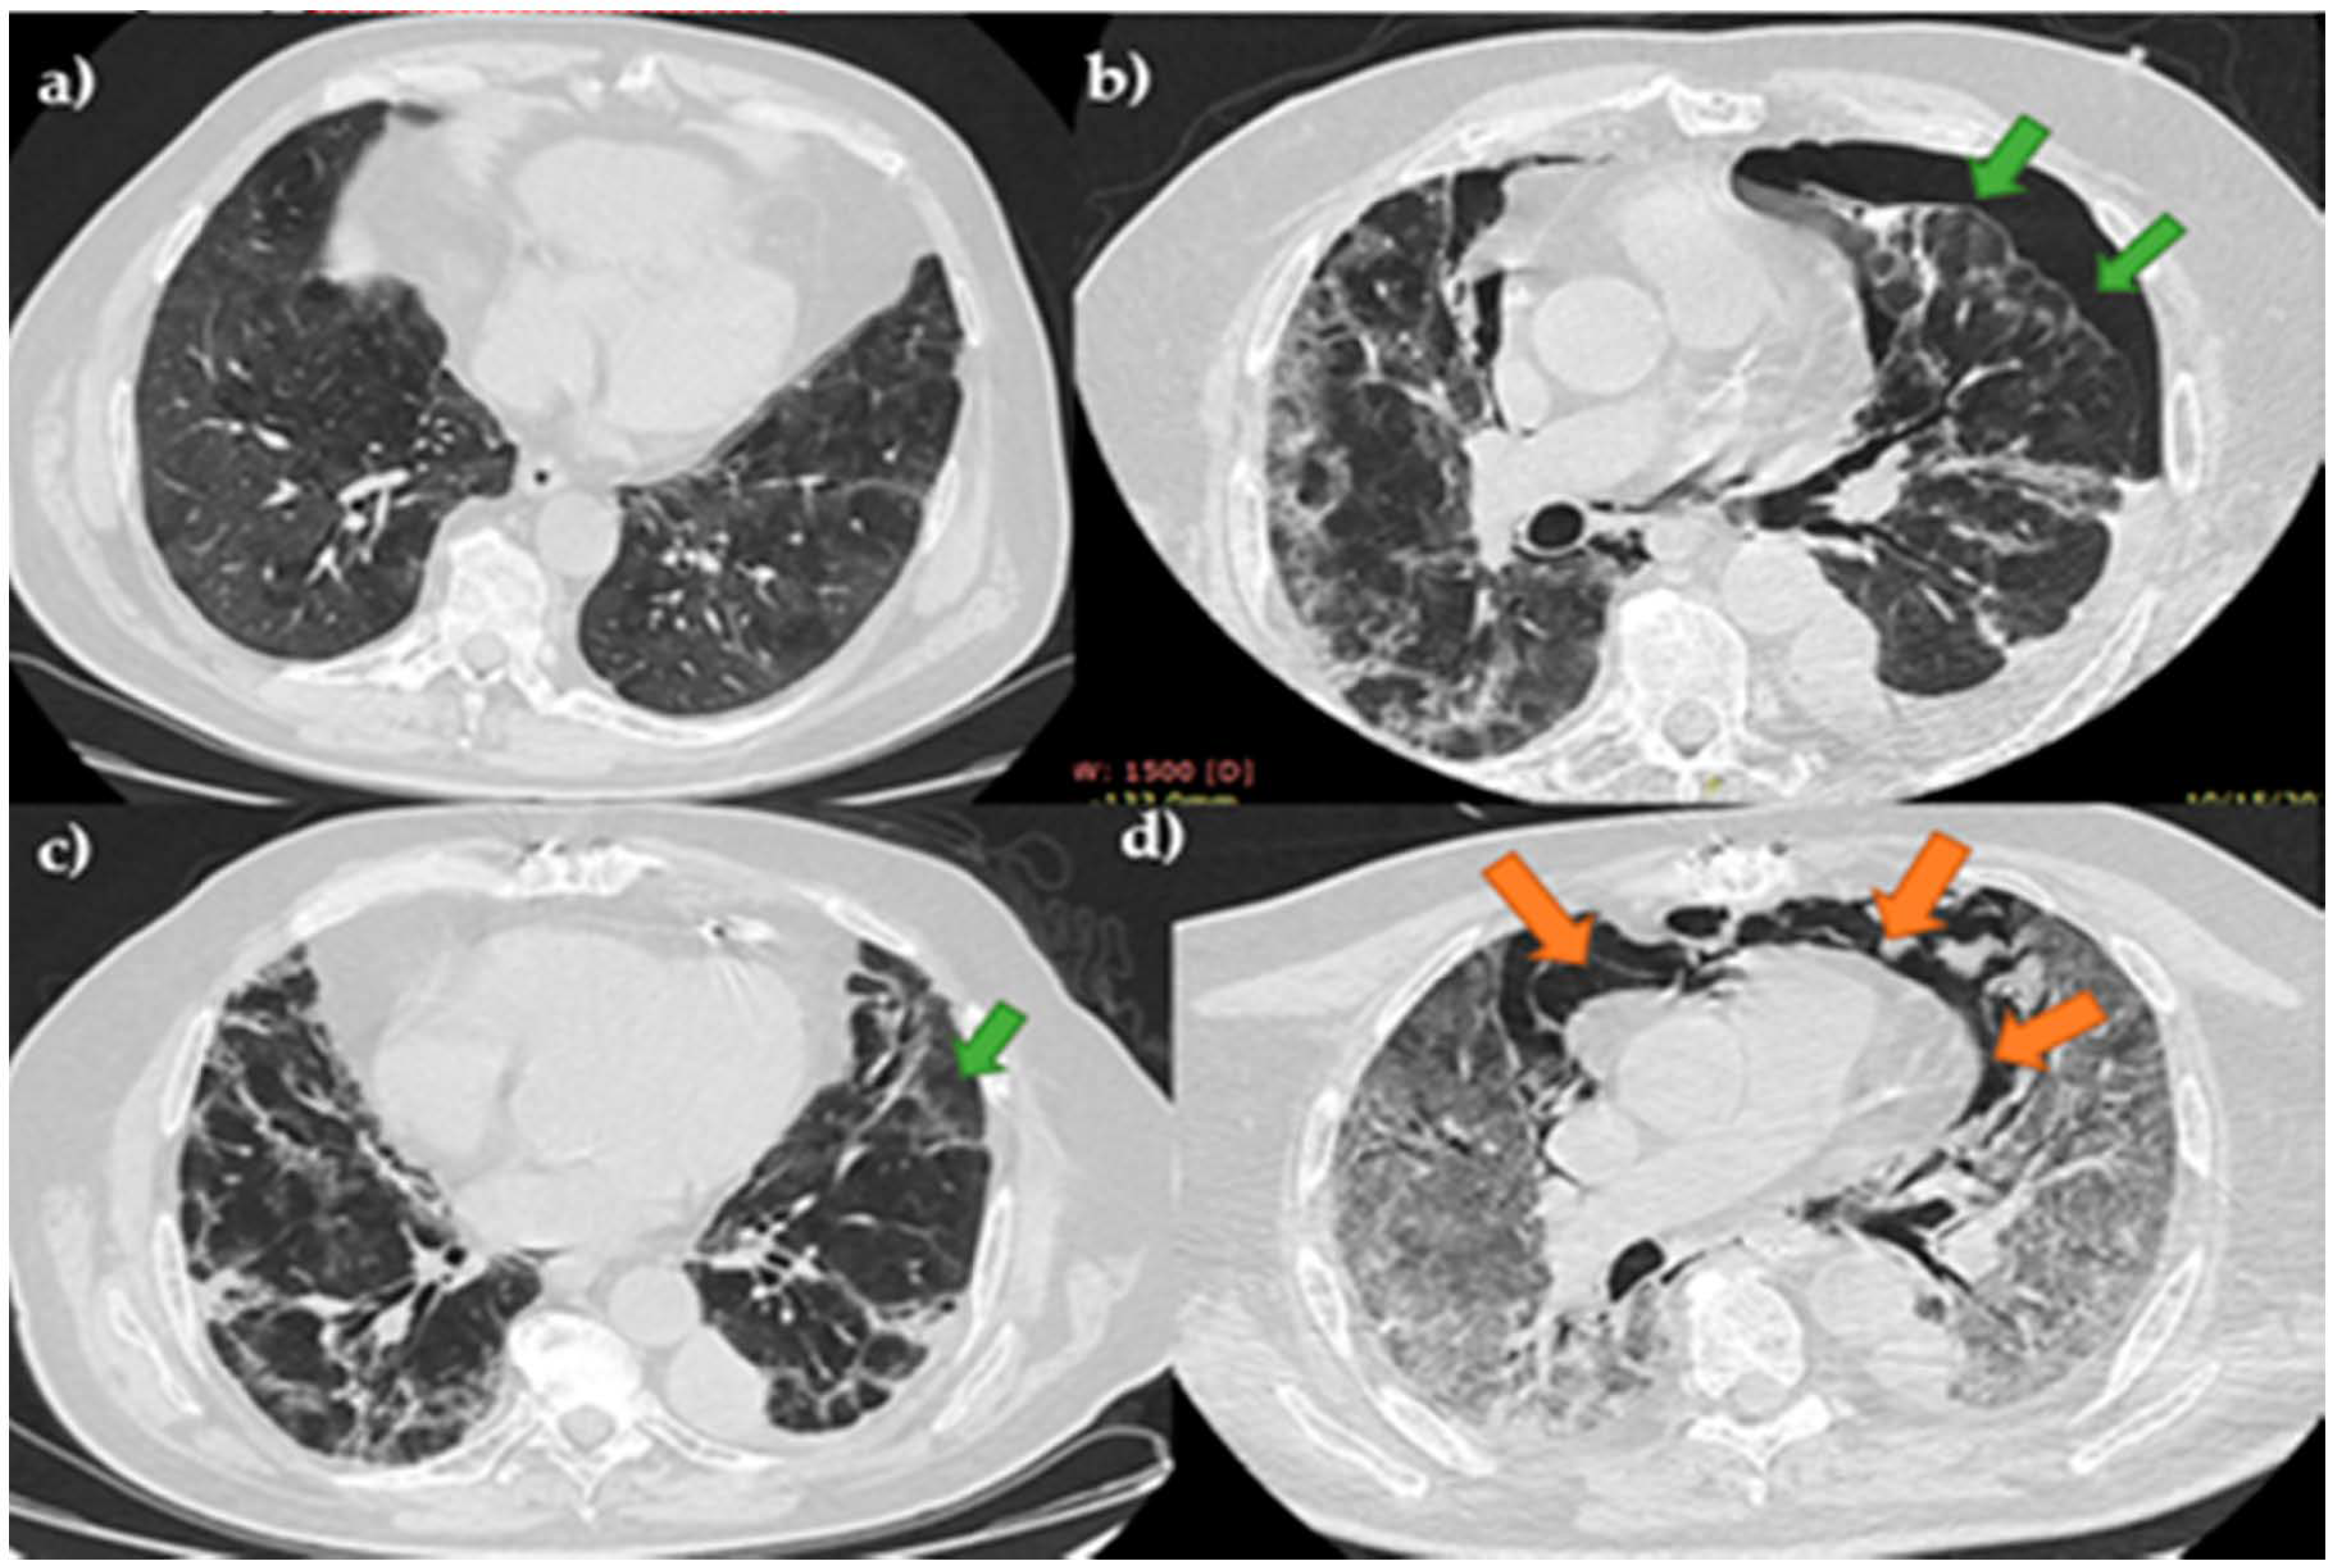

Spontaneous Pneumomediastinum, Pneumothorax, Pneumopericardium and Subcutaneous Emphysema—Not So Uncommon Complications in Patients with COVID-19 Pulmonary Infection—A Series of Cases

3. Results